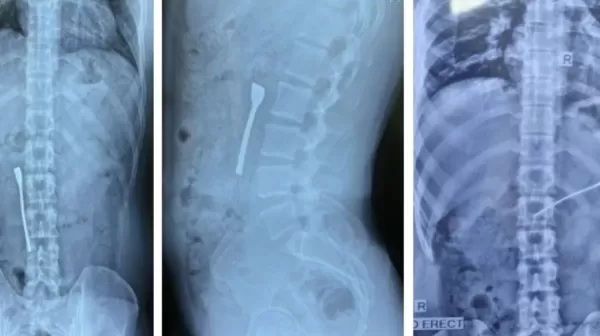

दिल्ली में एक युवक ने पानी पीते समय गलती से चम्मच निगल ली। डॉक्टरों ने एंडोस्कोपी करके 30 मिनट में चम्मच निकाली। फोर्टिस अस्पताल के डॉक्टरों के अनुसार चम्मच छोटी आंत में फंस सकती थी जिससे गंभीर खतरा हो सकता था। मरीज को ऑपरेशन के बाद अगले दिन छुट्टी मिल गई।

दिल्ली। एक युवक को जल्दबाजी में पानी पीना भारी पड़ गया। पानी से भरे गिलास में आठ सेंटीमीटर आकार की चम्मच पड़ी थी, युवक ने बिना देखे पानी पी लिया और पानी के साथ चम्मच भी उसके पेट में चली गई।